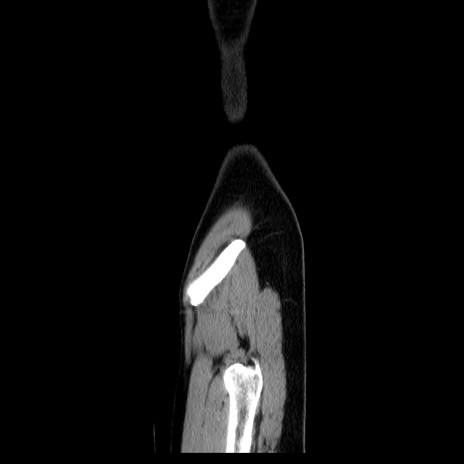

症例39(矢状断像)

【症例】40歳代女性

【主訴】上下腹部痛

【現病歴】2日目から下腹部痛あり。夜間は痛みで眠れなかった。昨日より上腹部痛と下痢が出現。臥位で痛みは軽快したため、休んでいた。本日になって臥位でも立位でも痛みが強くなってきたため救急要請。

【既往歴】子宮内膜症

【身体所見】部:平坦・軟、左上下腹部に圧痛あり、反跳痛あり。

【データ】WBC 21800、CRP 26.78

CT